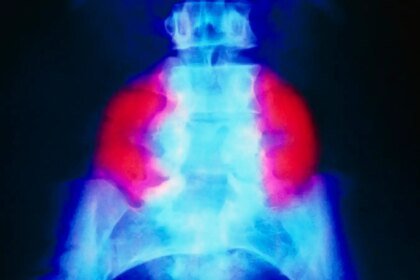

A false-colour X-ray exhibiting a big neural tube defect (crimson) on each…